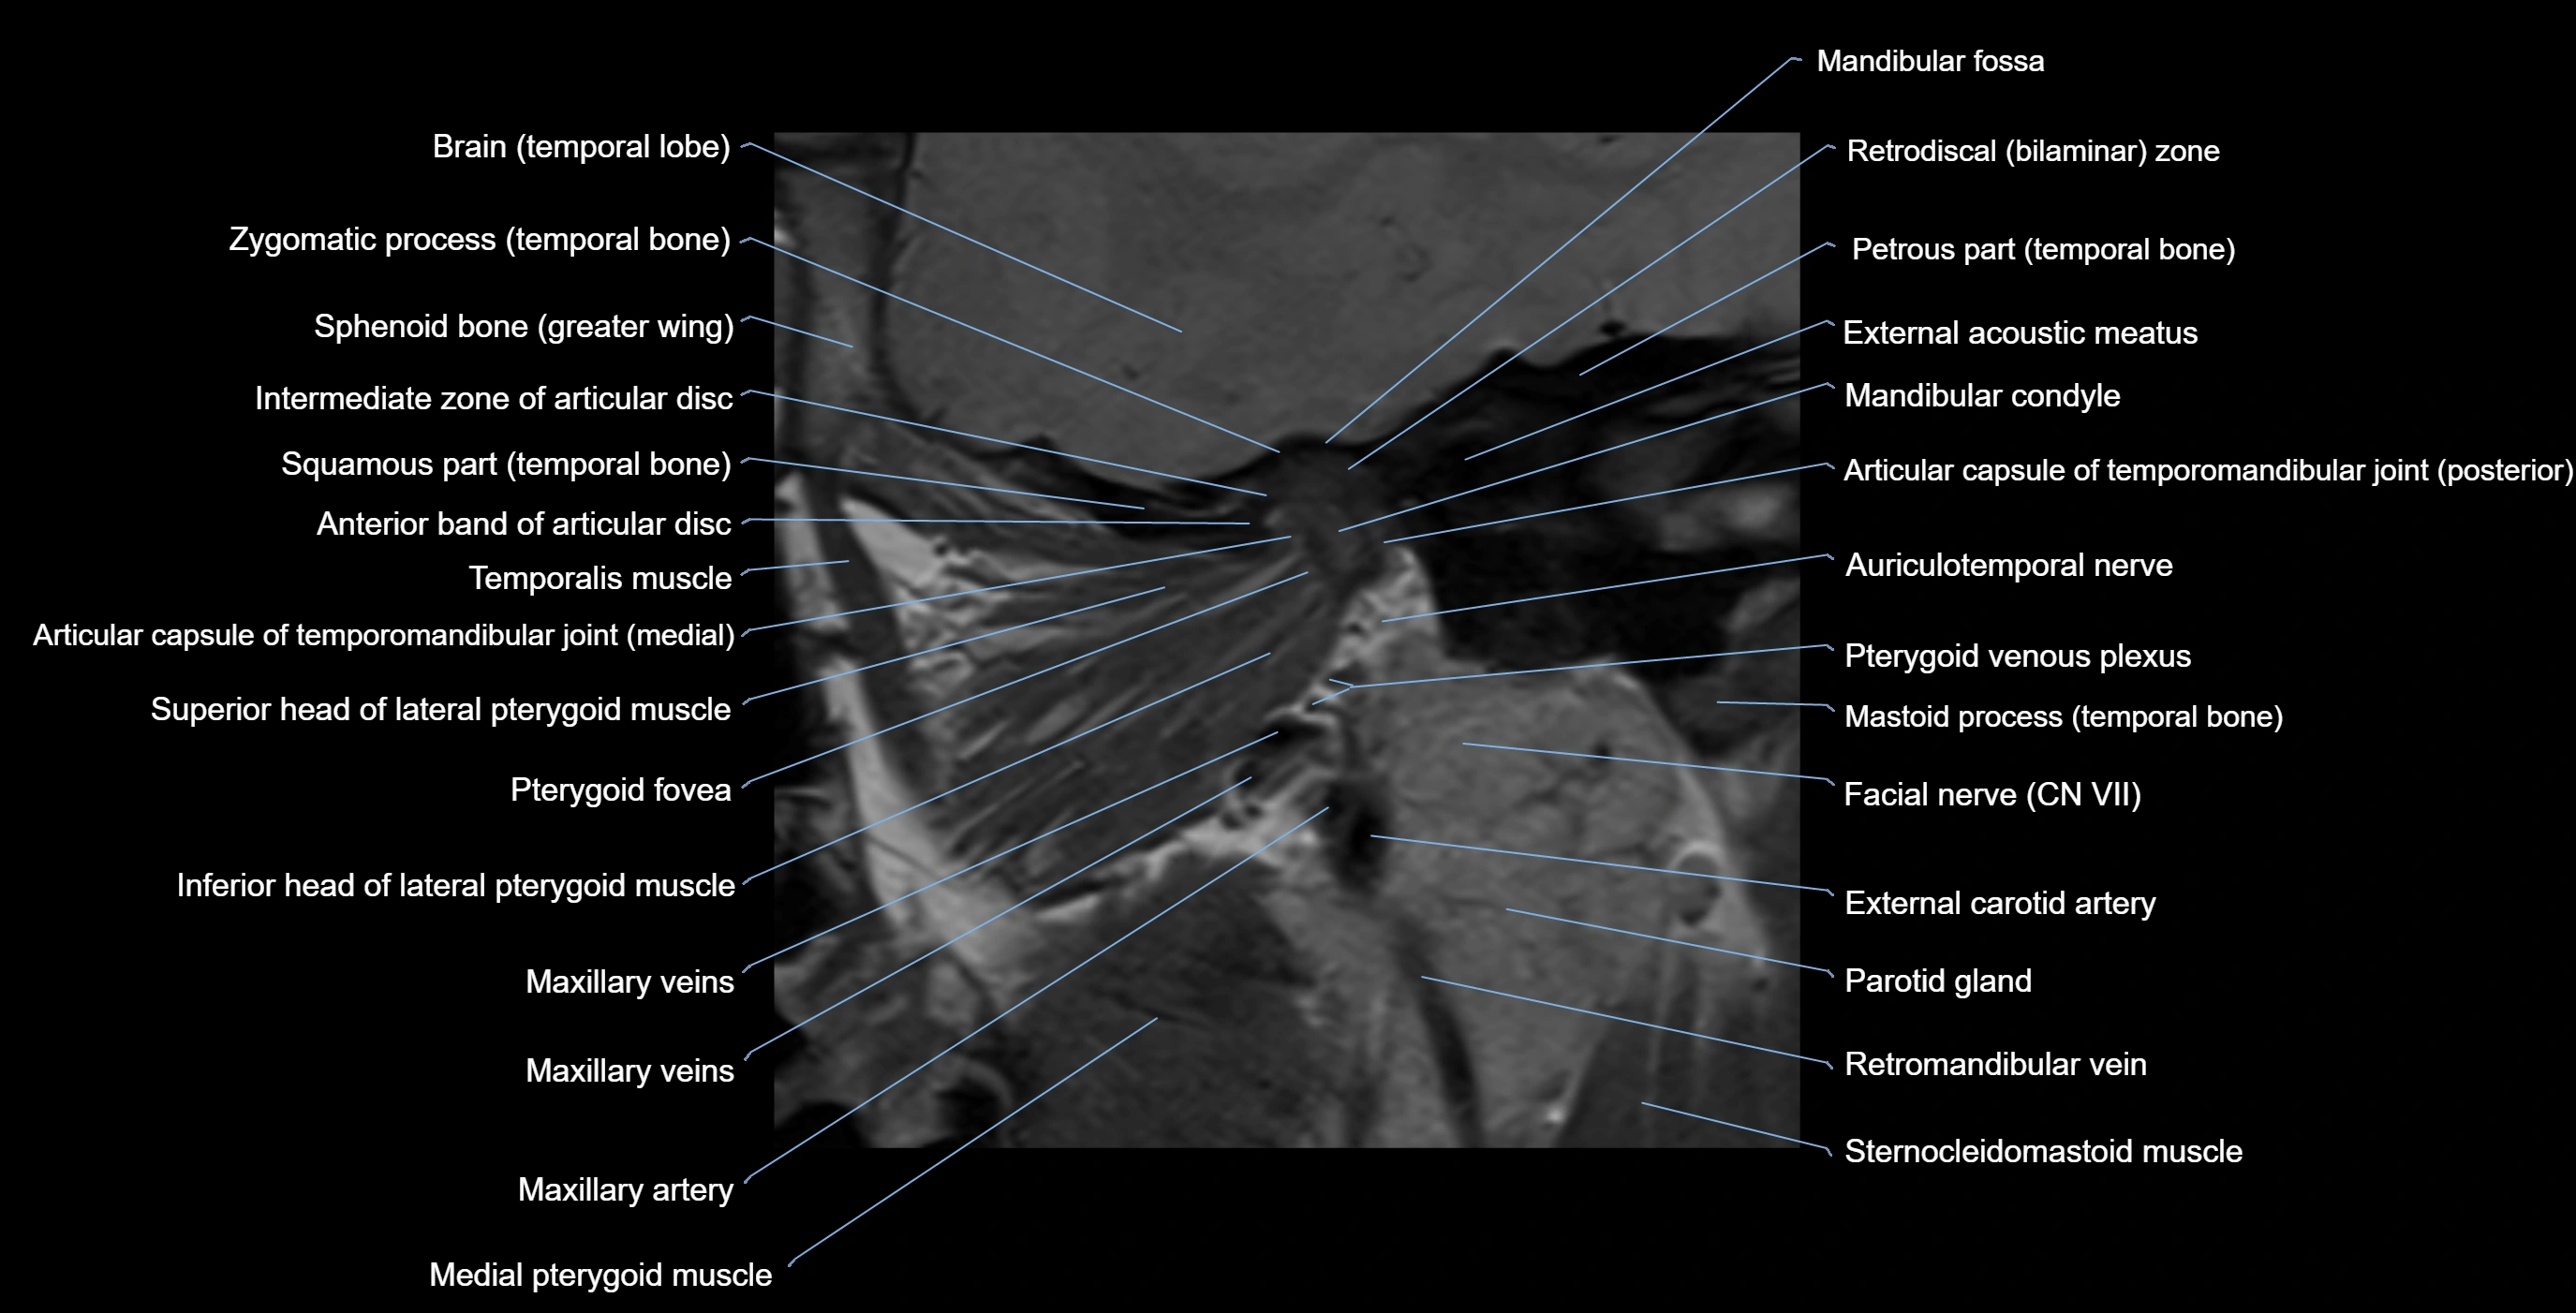

MRI appearance

T1-weighted images:

• Cortical bone: Low signal intensity

• Cancellous marrow: Intermediate to high signal depending on fatty content

• Teeth: Signal void structures

• Adjacent soft tissues: Normal gingiva and oral mucosa signal

T2-weighted images:

• Cortical bone and teeth: Low signal

• Marrow: Intermediate signal